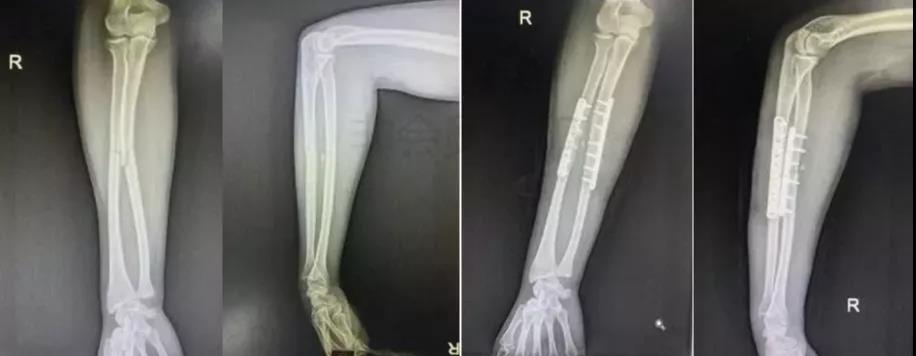

5)前臂骨折(尺骨,桡骨,或双骨折)

- 闭合或开放性骨折均争取伤后6-8h完成。

- 手术后延,尺骨-桡骨骨桥形成风险概率高。